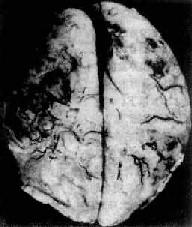

肉眼观,脑脊膜血管高度扩张充血,病变严重的区域,蛛网膜下腔充满灰黄色脓性渗出物,覆盖着脑沟脑回,以致结构模糊不清(图16-10),边缘病变较轻的区域,可见脓性渗出物沿血管分布。在渗出物较少的区域,软脑膜往往略带混浊。脓性渗出物可累及大脑凸面矢状窦附近或脑底部视神经交叉及邻近各池。由于炎性渗出物的阻塞,使脑脊液循环发生障碍,可引起不同程度的脑室扩张。

图16-10 化脓性脑膜炎

蛛网膜下腔内有多量脓液堆积以致大部分脑表面的沟回结构不清;脑膜血管高度扩张充血